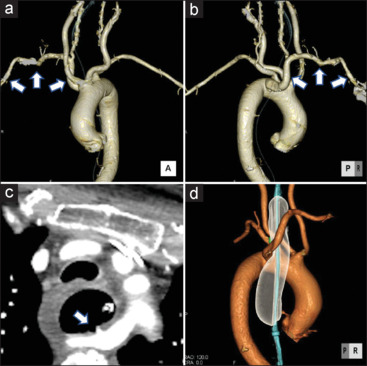

An aberrant right subclavian artery (ARSA) is a rare developmental anomaly wherein the right subclavian artery arises from the descending aorta as a fourth branch of the aortic arch. We present the case of ARSA in an 81-year-old woman who was injured in a motorcycle accident. The patient had a history of asymptomatic cerebral infarction, type 2 diabetes mellitus, and rheumatoid arthritis. She was diagnosed with spleen and liver injury, left renal injury, along with fractures in the rib, pelvic, vertebrae, and right tibia. On the 3rd hospitalization day, activated partial thromboplastin time (APTT) prolongation was observed, followed by sudden massive hematemesis and shock on the 39th day. We indicate sudden hematemesis and ARSA bleeding as the cause. We performed compression with a Sengstaken-Blakemore tube and coil embolization for hemostasis. Our findings show that the bleeding was mainly caused by nasogastric tube compression, prolonged APTT, and acquired hemophilia A.

畸形右锁骨下动脉(ARSA)是一种罕见的发育异常,即右锁骨下动脉从降主动脉发出,成为主动脉弓的第四分支。我们介绍了一例在摩托车事故中受伤的 81 岁女性的 ARSA 病例。患者有无症状脑梗塞、2 型糖尿病和类风湿性关节炎病史。她被诊断为脾脏和肝脏损伤、左肾损伤,以及肋骨、骨盆、椎骨和右胫骨骨折。住院第 3 天,观察到活化部分凝血活酶时间(APTT)延长,随后在第 39 天突然出现大量吐血和休克。我们指出突然吐血和 ARSA 大出血是病因。我们用 Sengstaken-Blakemore 管进行压迫,并用线圈栓塞止血。我们的研究结果表明,出血主要是由鼻胃管压迫、APTT延长和获得性血友病A引起的。